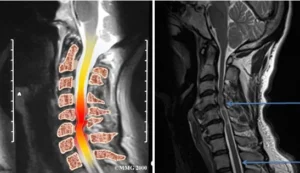

mielopatia cervical é a lesão da medula espinhal, devido a compressão da medula espinal na altura do pescoço,  em conseqüência da “espondilose” ou artrose cervical intervertebral que diminuem o espaço que a medula ocupa no canal vertebral. Ela pode se manifestar com fraqueza, espaticidade, perda de equilíbrio e incontinência urinária.

O processo ocorre devido a hipertrofia de ligamento, facetas  articulares e protusões de disco que levem a redução do espaço que a medula ocupa no canal vertebral.

• Ressonância magnética – avalia a estrutura da coluna em relação aos tecidos moles e também o grau de sofrimento medular